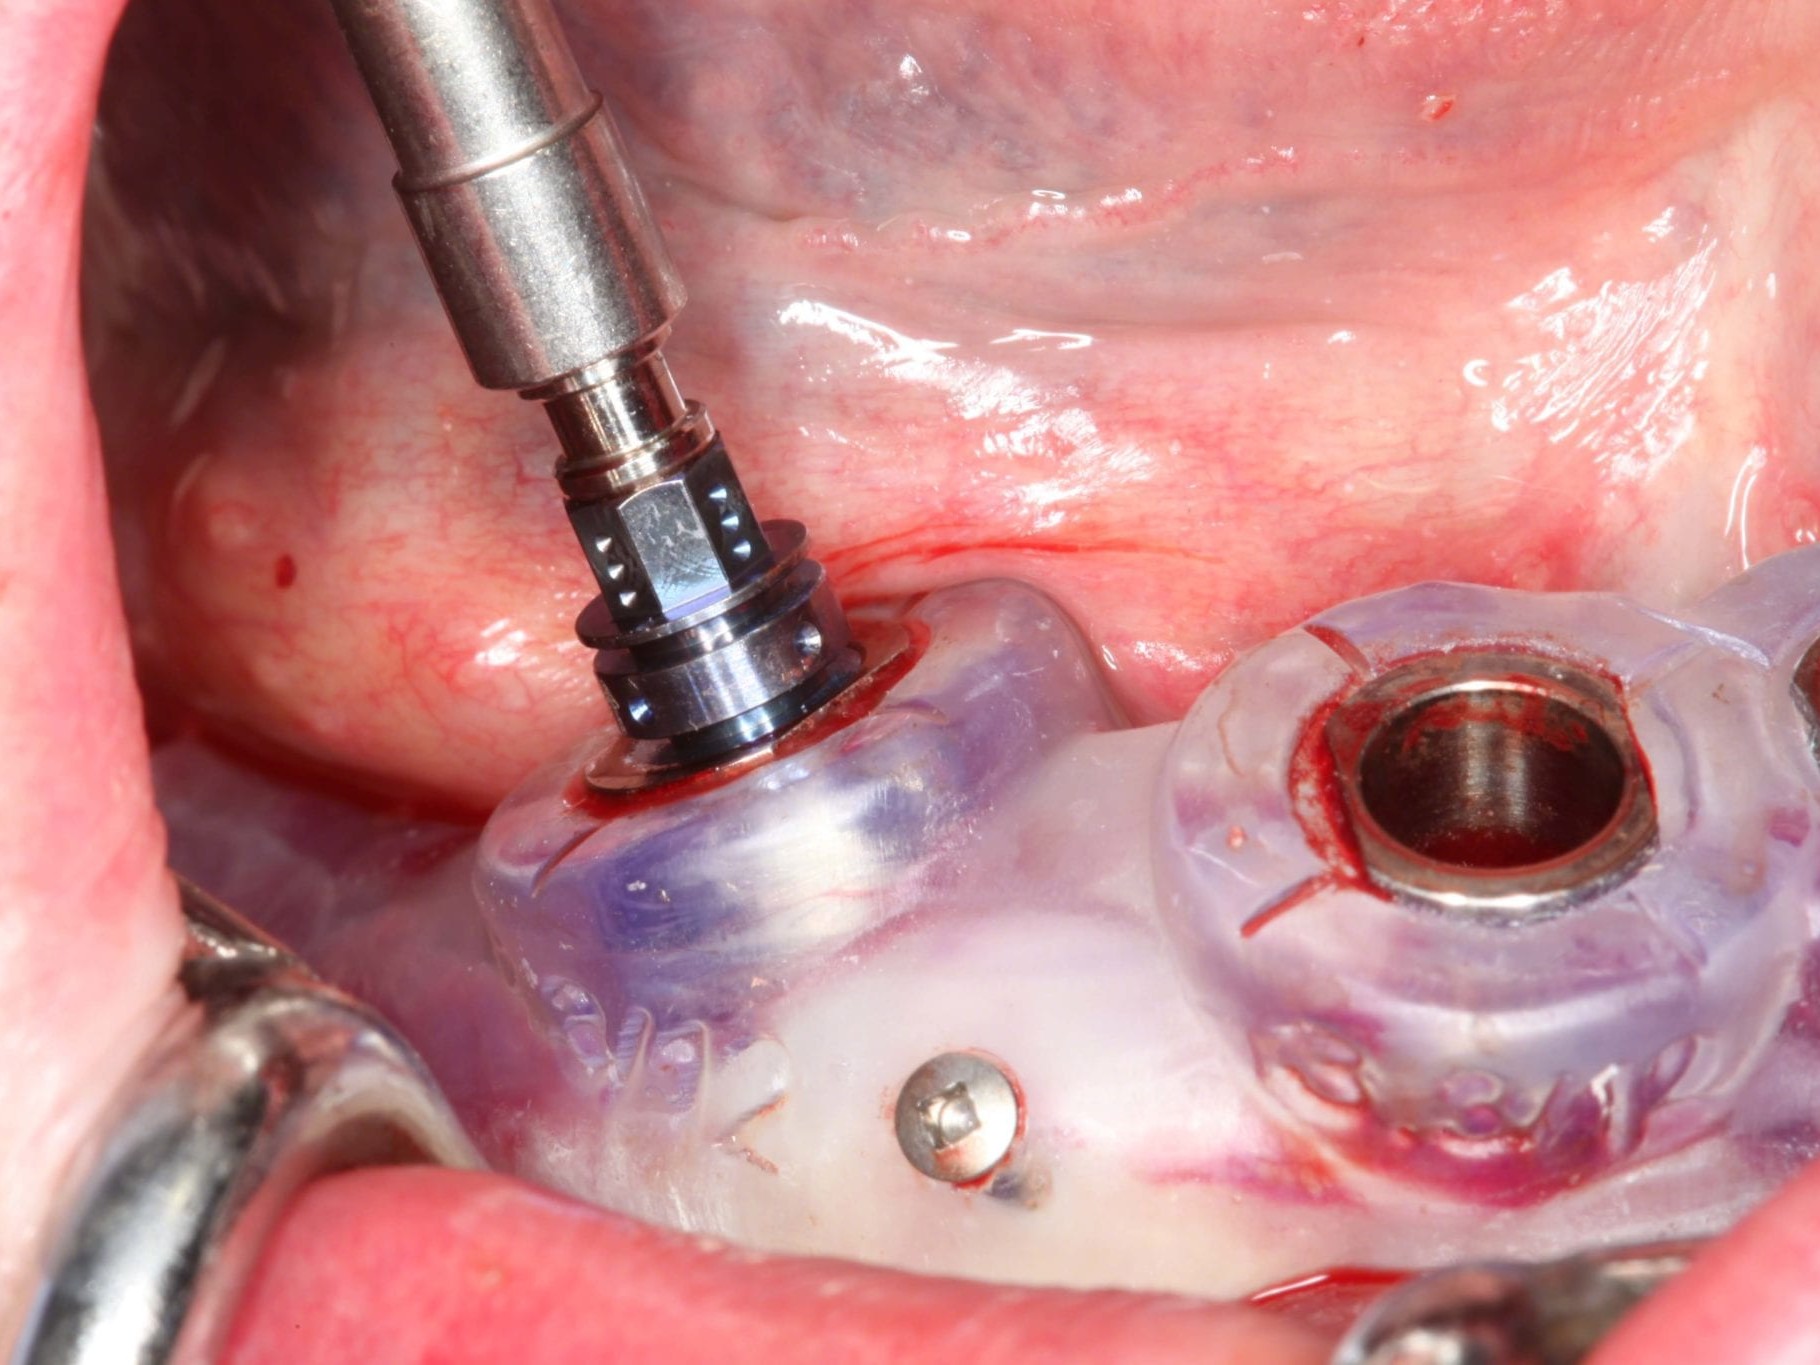

In Lokalanästhesie unter anästhesiologischem Standby mit intravenöser Antibiose mittels Clindamycin 600 mg 2mal/d wurde die Bohrschablone eingesetzt und mit Osteosyntheseschrauben fixiert (Abb. 8). Der Eingriff erfolgte nahezu flapless und somit transgingival. Nun erfolgte die Umsetzung des Straumann Hülse-in-Hülse-Konzeptes. Der Zylinder des Bohrlöffels wird in die an der Bohrschablone fixierten Hülse (Ø 5 mm) in den geplanten Regionen eingeführt. Für jeden Bohrerdurchmesser (Ø 2,2 mm und Ø 2,8 mm) ist ein entsprechender Bohrlöffel erhältlich. Jeder Bohrlöffel besitzt an seinen Enden Zylinder unterschiedlicher Höhe, die entsprechend chirurgischem Protokoll angewendet werden. Es wurden sämtliche Bohrstollen protokollgemäß aufbereitet (Abb. 9-11). Nach der Aufbereitung der Bohrstollen für die angulierten Implantate (Abb. 12-14) wurden die Straumann Bone Level Tapered Implantate (ø 3,3 mm) in regio 035 (Länge 10 mm) und 045 (Länge 12) gesetzt (Abb. 15). Abschließend wurden sämtliche Endpositionen der Implantate in regio 035 und 045 anhand der Lasermarkierungen am Übertragungsteil betreffend ihrer orovestibulären Ausrichtung exakt überprüft (Abb. 16). Nach Entfernung der Einbringhilfen und der Osteosyntheseschrauben konnte die Bohrschablone wieder entnommen werden. In regio 032 und 042 wurden nun die durchmesserreduzierten Straumann NNC (ø 3,3 mm Länge 12 mm) Implantate inseriert (Abb. 17, 18). Bei diesen Implantaten bedurfte es keiner Ausrichtung bezogen auf die orofasziale Ausrichtung. Hier musste die Insertionstiefe bezogen auf das NNC-Implantat beachtet werden (Abb. 19). Die NNC-Implantate wurden mit den entsprechenden Klebebasen versehen (Abb. 20). Danach wurden in regio 035 und 045 auf die Pro Arch Sekundärteile die dazugehörigen Retentionskappen (Abb. 21), die zur Vergrößerung der Oberfläche mit 120 μ Aluminiumoxyd abgestrahlt wurden, eingesetzt. Es erfolgte der typische Naht-Wund-Verschluss mit Einzelknopfnähten. Zum Abschluss erfolgte das prothetische Procedere mit der Eingliederung des Interimszahnersatzes in Okklusion (Abb. 22). Hierfür wurden die Retentionskappen und die Klebebasen mit dem Sofortprovisorium über ein selbsthärtendes fluoreszierendes kaltpolymerisierendes Paste-Paste-Kartuschensystem fixiert, dieser Zahnersatz extraoral versäubert (Abb. 23) und in der Mundhöhle refixiert (Abb. 24). Die Schraubenkanäle wurden mit Kunststoff verschlossen (Abb. 25). Abschließend erfolgte die radiologische Kontrolluntersuchung (Abb. 26).